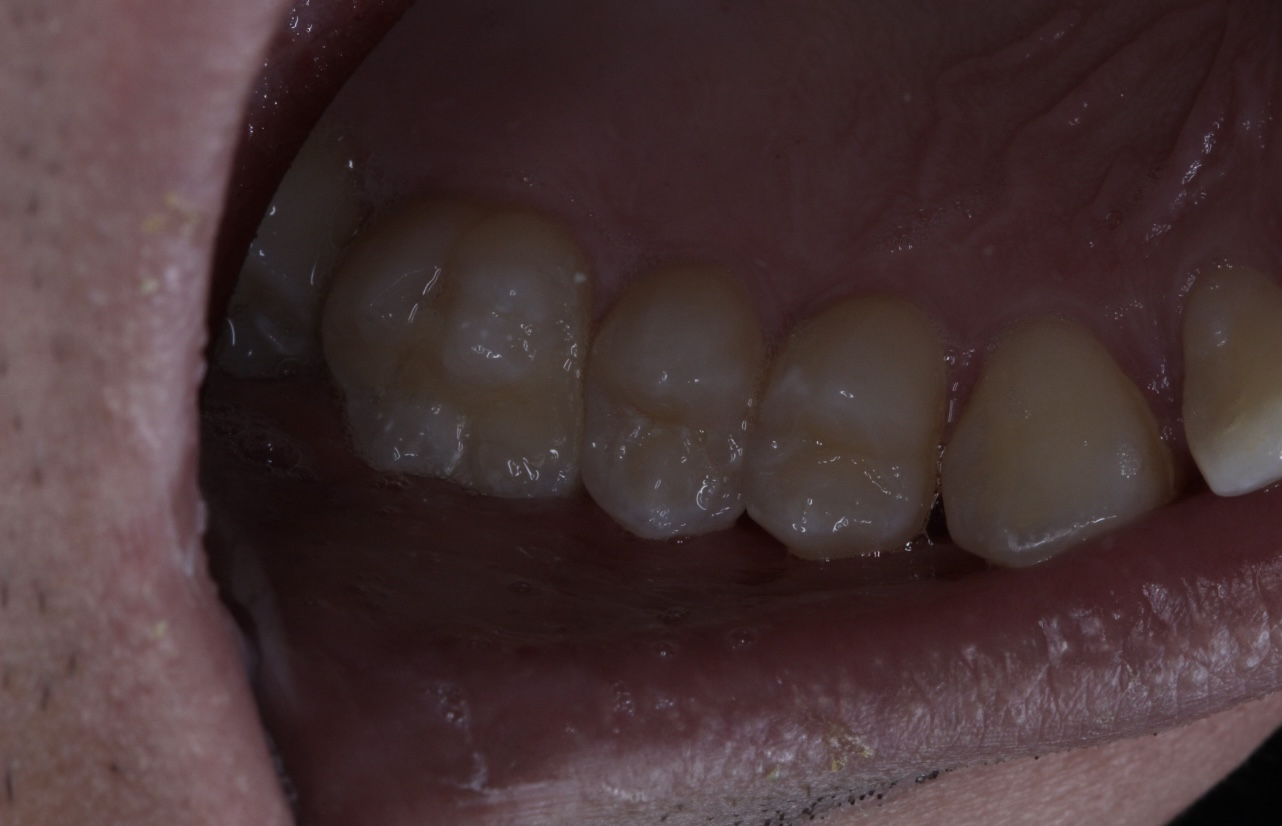

2.jpg 357Кб, 2560x900

2560x900

1.jpg 788Кб, 2560x1429

2560x1429

Двачь помогачь.

Есть одна ебанутая, довела зубы до такого состояния. К доктору идти боятся.

Собственно вопрос, можно ли туда хуй совать что можно сделать в домашних условиях. Она ведёт эталонный нищенский хиканский образ жизни, возможет ли это быть результат диеты или "плохой" воды? Зубы чистить не умеет, но не думаю что если научится, это сильно изменит ситуацию.